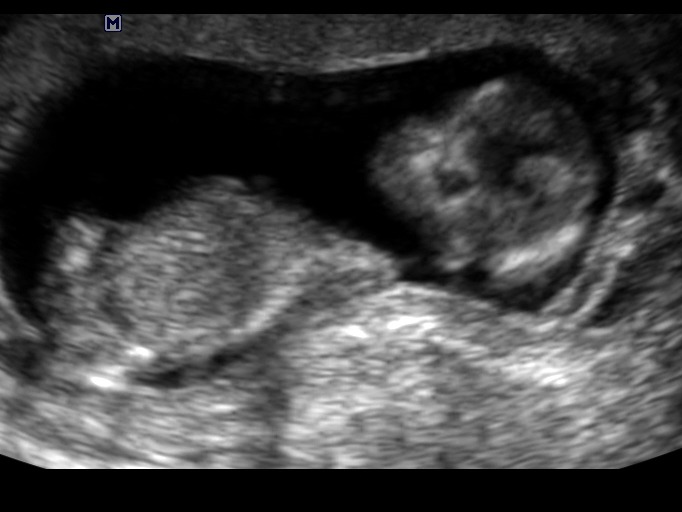

13 weeks...is this a girl most likely? Or boy?